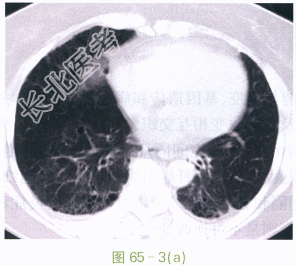

- [材料题] 患者,女性,65岁。胸闷、气急、气喘、咳嗽数年,近日加重。影像学资料如图65-1~图65-3所示。

- 简答题1、请问特发性肺间质纤维化临床特点是什么?

- 简答题2、请问特发性肺间质纤维化的诊断依据是什么?

- 简答题3、请问特发性肺间质纤维化的治疗方法有哪些?